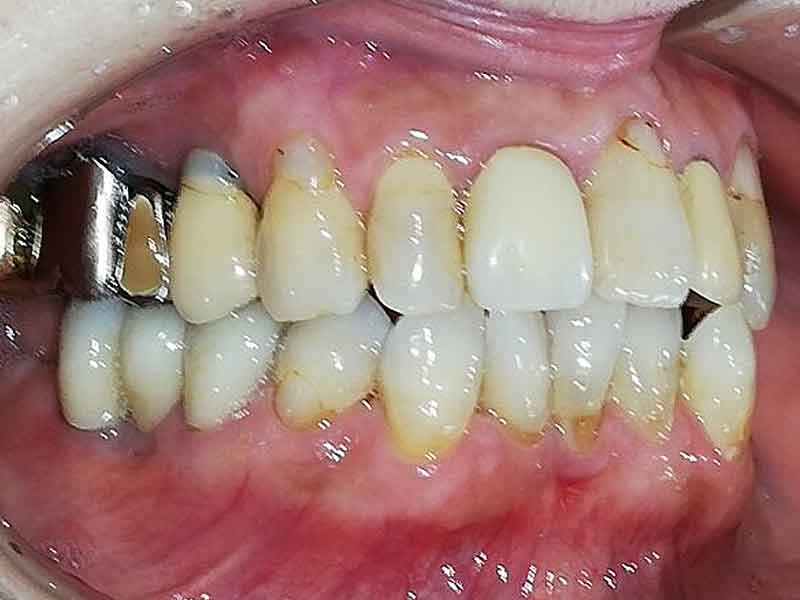

Before

術前

右下奥歯3本を治療

破折して保存不可能な歯根を抜いて、保存可能な歯根を残してブリッジを作成しました。